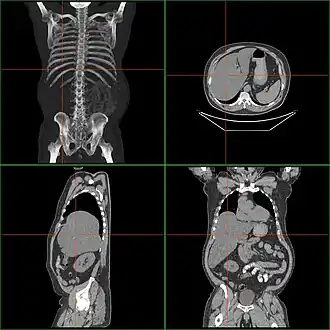

Tomographie d'une hépatomégalie.